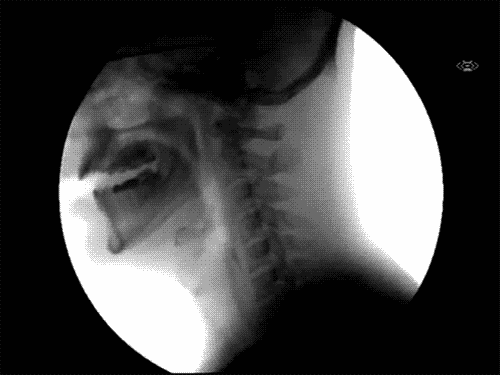

Here’s how you swallow.